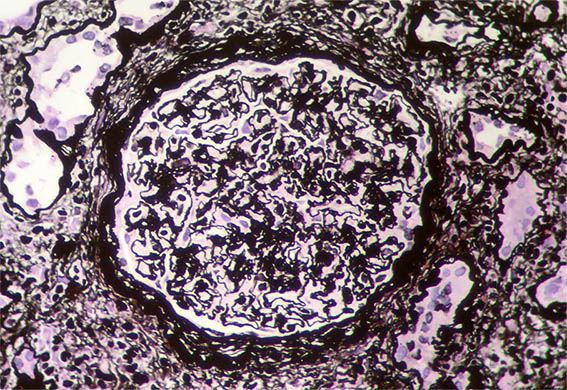

Figure 7. Methenamine-silver stain, X400. Thick and wrinkled basement membranes, suggestive of ischemic changes.